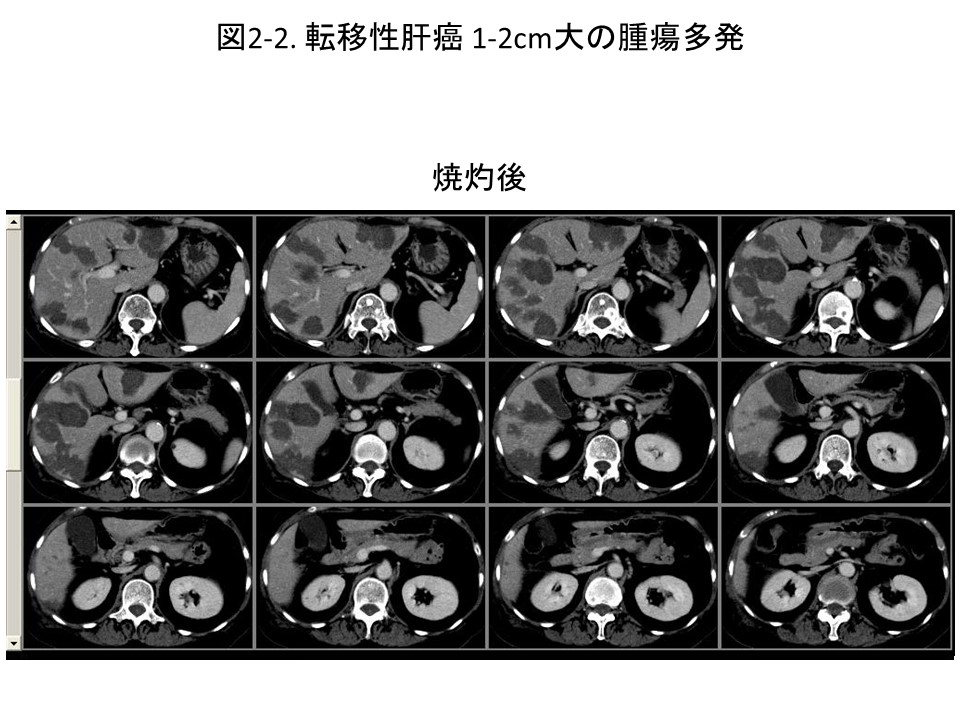

無痛RFAの適応・・・転移性肝癌に関して

転移性肝癌とは、肝臓以外の臓器にできた癌(原発巣)が肝臓に転移したものを指します。ほぼすべての癌種において、肝臓へ転移する可能性がありますが、実際には消化器系の癌(大腸がん、胃がん、膵がん、胆のうがんなど、)乳癌、肺癌、婦人科系の癌、腎癌などが肝臓への転移を認めることが多いと報告されています。当院ではそのような転移性肝癌についても、積極的に無痛RFAを行っています。転移性肝癌は肝硬変を合併していないため、より大きな、そして、たくさんの腫瘍を焼灼することが可能です(図1-2)。しかし、転移性肝癌に対する無痛RFAはまだ歴史が浅く、外科的手術、抗がん剤治療、無痛RFAのいずれが最良なのか結論がでておりません。転移性肝癌の治療に関しては、無痛RFAのみに固執せず、必要とあれば、抗がん剤治療、放射線治療等をうまく組み合わせて、患者さんがより元気に長生きできるよう努めております。肝内の腫瘍量減退が予後延長に結びつくと予想される場合は、積極的に集学的治療の一環として、無痛RFAをおこなっています。 (全身状態に実施不可能な場合もあります。)そのため、明確な腫瘍の大きさ、腫瘍の個数の制限を設けていません。お手数ですが、ご自身の転移性肝癌の状態が無痛RFAの適応かどうか、個別に外来に受診していただきご相談いただければ幸いです。大まかな目安としては、最大径5cmの場合は3個程度まで、最大径2cmの場合は10個程度までとなります。